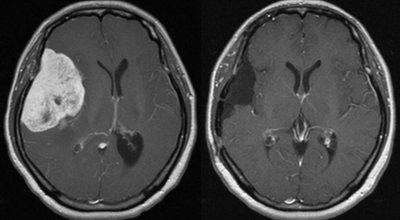

뇌종양이란 뇌 조직이나 뇌를 싸고 있는 막에서 발생한 종양과, 머리뼈나 주변 구조물로부터 멀리 떨어진 부위에서 뇌 조직이나 뇌막으로 전이된 종양을 의미해요. 뇌종양은 양성과 악성으로 나눌 수 있답니다. 양성 뇌종양은 성장 속도가 느리며 주위 조직과의 경계가 뚜렷해요. 양성 뇌종양은 수술 이외의 다른 치료 없이 완치되는 경우가 흔하고, 대부분 천천히 자라기 때문에 수술하지 않고 경과를 관찰하기도 해요.

악성 뇌종양은 뇌암이라고도 하고, 성장 속도가 빠르며 주위 조직으로의 침투 역량이 강해요. 이에 따라 정상 뇌 조직으로 침윤되고 정상 뇌 조직과의 경계가 불분명해서 치료가 어려운 편이예요. 악성 뇌종양은 주변의 정상 뇌 조직을 빠른 속도로 파괴해요.